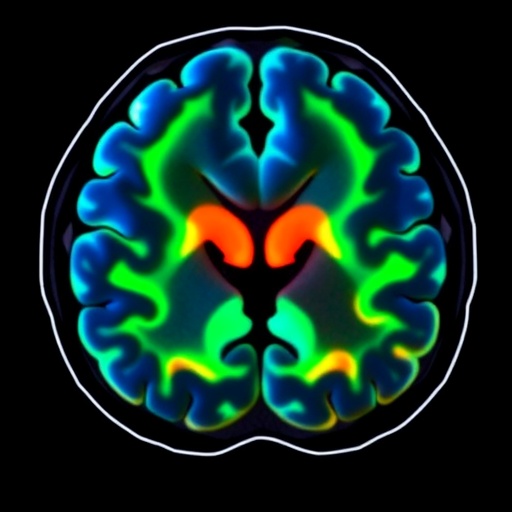

The imaging characteristics of neuroleukemiosis can exhibit a spectrum of presentations on modalities such as MRI and CT scans. Typically, MRI serves as the preferred imaging technique due to its superior ability to visualize the brain’s structures and potential abnormalities. Clinicians and radiologists should familiarize themselves with the imaging priors indicative of leukemic infiltration so that they can differentiate neuroleukemiosis from other more prevalent conditions, such as infections or other types of tumors.

In a recent scholarly article, the authors Dagar, Rahim, and Koehler delve into the specifics of neuroleukemiosis, detailing imaging characteristics and clinical presentations observed in young patients. Such studies are of paramount importance as they illuminate how neuroleukemiosis can represent a relapse of acute myeloid leukemia, offering a profound insight into the disease’s progression and associated complications.